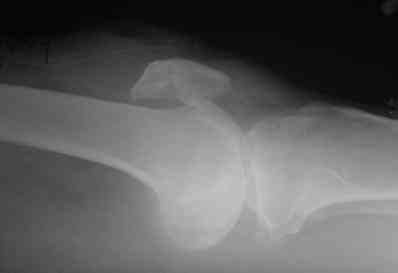

В приложении фото пациента с переломом надколенника 3 месячной давности. После мобилизации отломков, 4 главой мышцы бедра и полного разгибания голени оставался диастаз между костными фрагментами в 2 см. В связи с этим наложили модуль из аппарата Илизарова - 2 опоры и 2 спицы (в верхнем полюсе надколенника и верхней трети большеберцовой кости). Очень медленно (в течение 15 минут) путем накручивания гаек на стержнях растянули 4 главую мышцу бедра и устранили диастаз. Аппарат демонтировали и выполнили остеосинтез <стягивающей петлей>. Через 6 месяцев фиксаторы удалены. Автор данного <хирургического трюка> профессор из Австрии Vilmos Vecsei (<Гений ортопедии>, 2004, № 4, С. 94-95). Ваш случай не совсем идентичный по давности травмы и малой величине дистального отломка, но описанный <трюк> может оказаться полезным и при выполнении операции, которую рекомендует Джолдас.